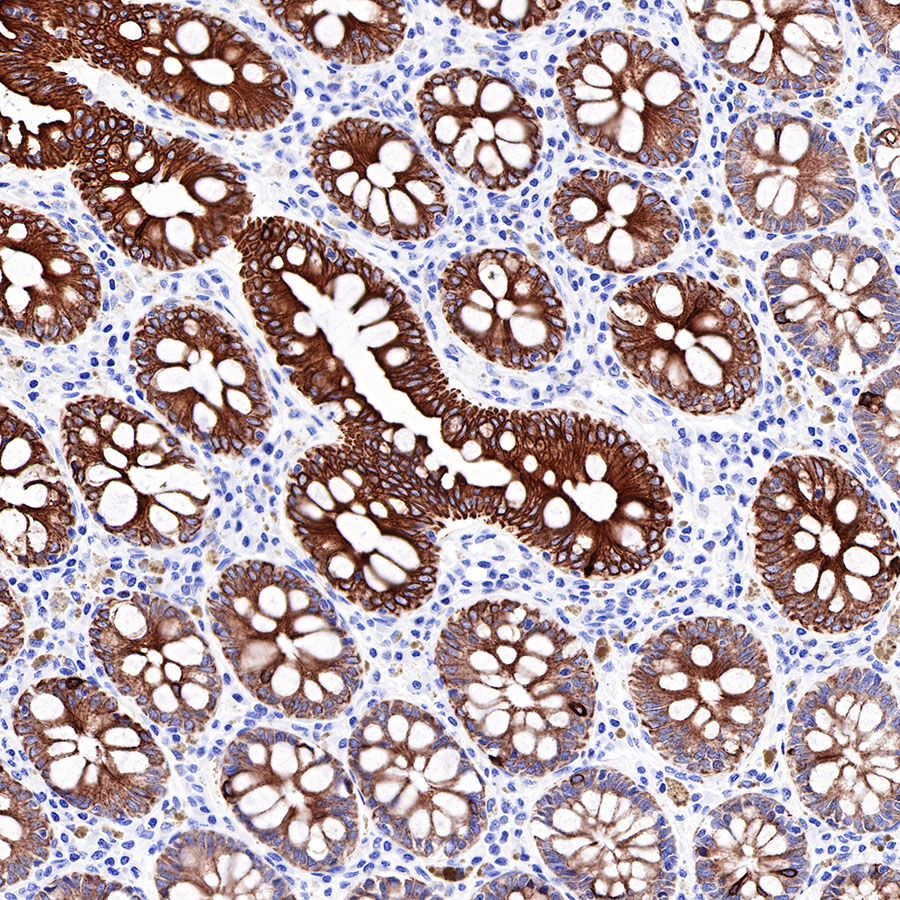

| IHC-P |

1:500-1:2000 |

Background

CK-LMW is low molecular weight cytokeratins and is expressed in monolayer or glandular epithelium of normal or tumor tissues, such as thyroid, breast, gastrointestinal or respiratory epithelium. It is expressed in adenocarcinoma and the vast majority of nonkeratinizing squamous cell carcinoma, but not in keratinizing squamous cell carcinoma. It combined with CK5/6 for diagnosis of adenocarcinoma and squamous carcinoma.